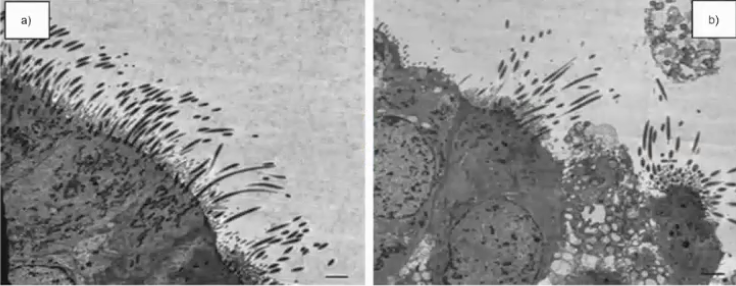

Escheria E. coli EPEC- Gram (-) rod that is lactose fermenting oxidase negative and causes A/E lesions and diarrhea in infants and secretes its own receptor

Escheria E. coli EAEC (O104:H4) - Gram (-) rod that is lactose fermenting oxidase negative and causes stacked brick on epithelial cells and chronic , non bloody diarrhea